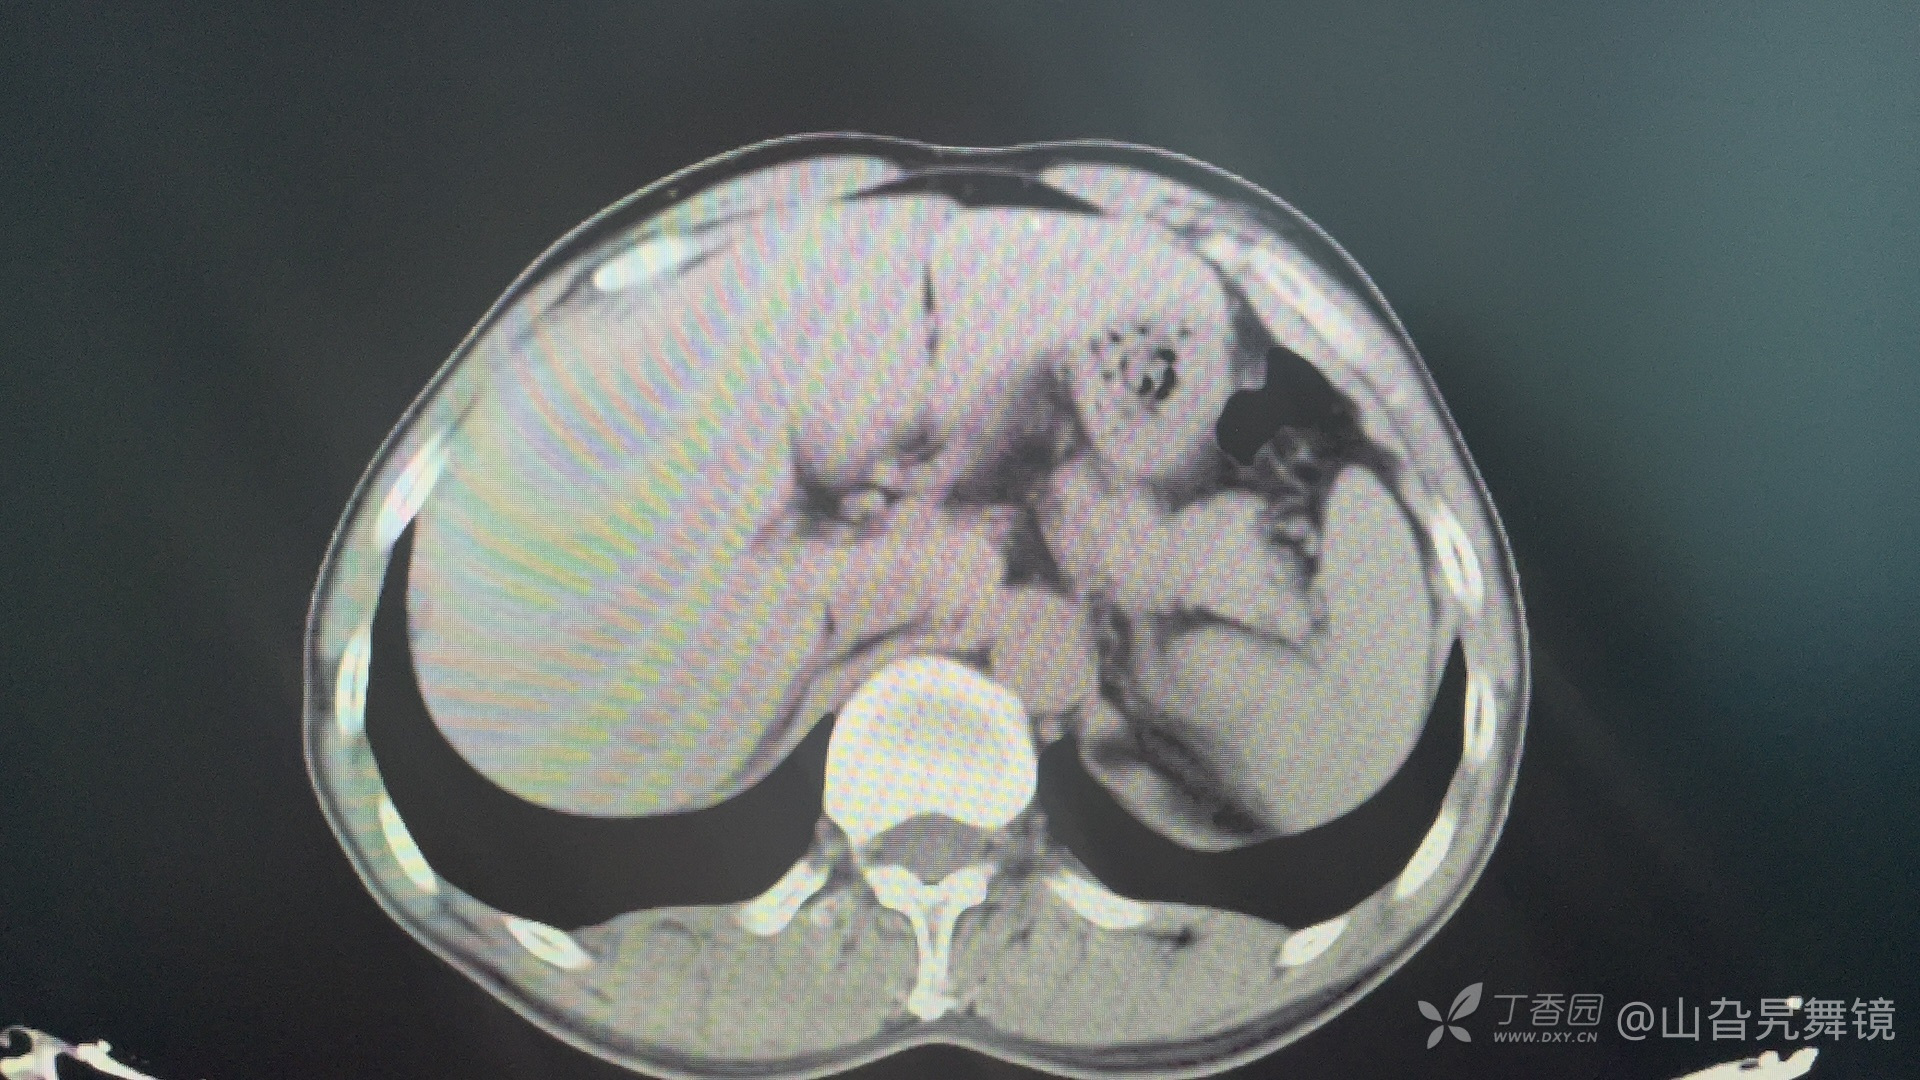

泌尿系平扫